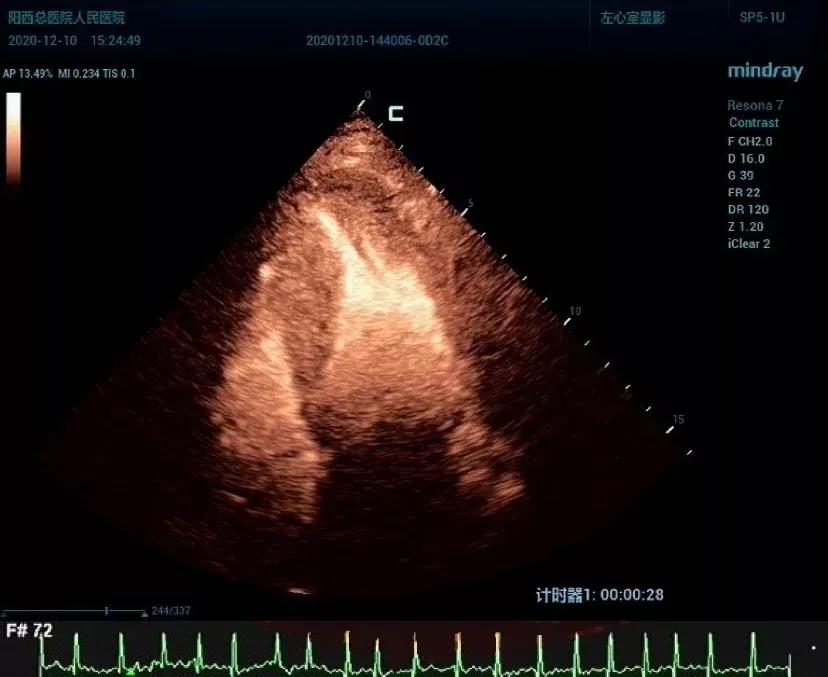

12月10日,一位70岁男性患者,因反复劳力性胸闷痛7天入院。经了解既往无高血压、糖尿病史。心电图检查发现患者胸前导联ST段下移,T波深倒,提示心肌缺血,冠脉造影未见异常,行常规心超考虑“心尖肥厚型心肌病”。因心内膜边界欠清晰,为进一步佐证临床医师的诊断,韦教授建议行左心声学造影。造影结果心肌明显增厚,心尖部呈“核桃尖”样改变,心腔接近闭塞,造影检查不仅准确测量得出心肌厚度,同时发现常规心超检查没有发现的小室壁瘤。最终诊断“心尖肥厚型心肌病并室壁瘤形成”,这一诊断为临床治疗和预后评估提供非常重要的信息。

左心声学造影是一项相对较新的心脏超声技术,能够清晰显示心内膜边界,主要用于心脏结构和功能的评估,包括精确测量左心室容积及射血分数,明确心脏解剖结构异常如左心室心尖畸形、左心室心尖肥厚、左心室心肌致密不全、左心室心尖血栓、左心室室壁瘤、室壁穿孔、心脏内的团块影等。心尖肥厚的肥厚型心肌病在总体肥厚型心肌病中占7%,但传统的体表超声心动图由于不能完全显示心尖而有约15% 的漏诊率。当临床上对心尖肥厚型心肌病而不能明确诊断或排除时,应进行声学造影检查。患者经韦教授丰富的临床经验确诊后,即实行对症治疗,取得确切疗效。